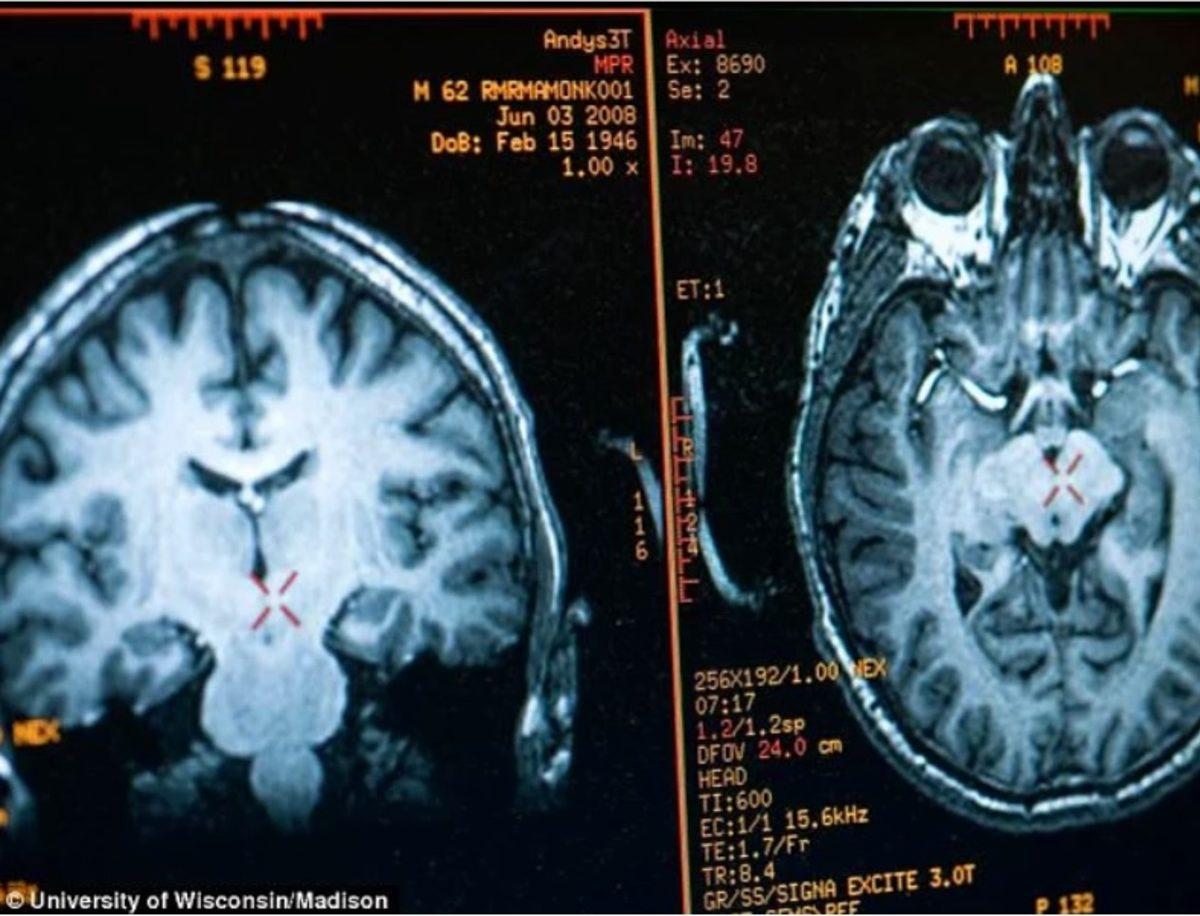

Kendisinde tespit edilen yüksek oranda mutluluğun resmi sonuçlarına gelirsek; Matthieu Ricard, bundan birkaç yıl önce Wisconsin Üniversitesi’nde kendi gibi düzenli olarak meditasyon yapan birkaç kişiyle birlikte yürütülen bir araştırmanın deneği olmuş ve kafatasına tam 256 elektrot yerleştirilerek MR görüntülerine bakılmış.

Sonuçlanan tarama sonuçları, deneyi yapanları bir hayli şaşırtmış. Çünkü Ricard'ın mutluluk hormonlarının seviyesi, yaşadığı himalayalar kadar yükselmiş. Beynindeki şükretmek ve zevk almak ile ilgili alanların "anormal" derecede gelişmiş ve normalden daha büyük olduğu, beynin ön sol lobunda ise negatif duyguları engellemeye meyilli ve mutluluk veren geniş bir alan olduğu tespit edilmiş.